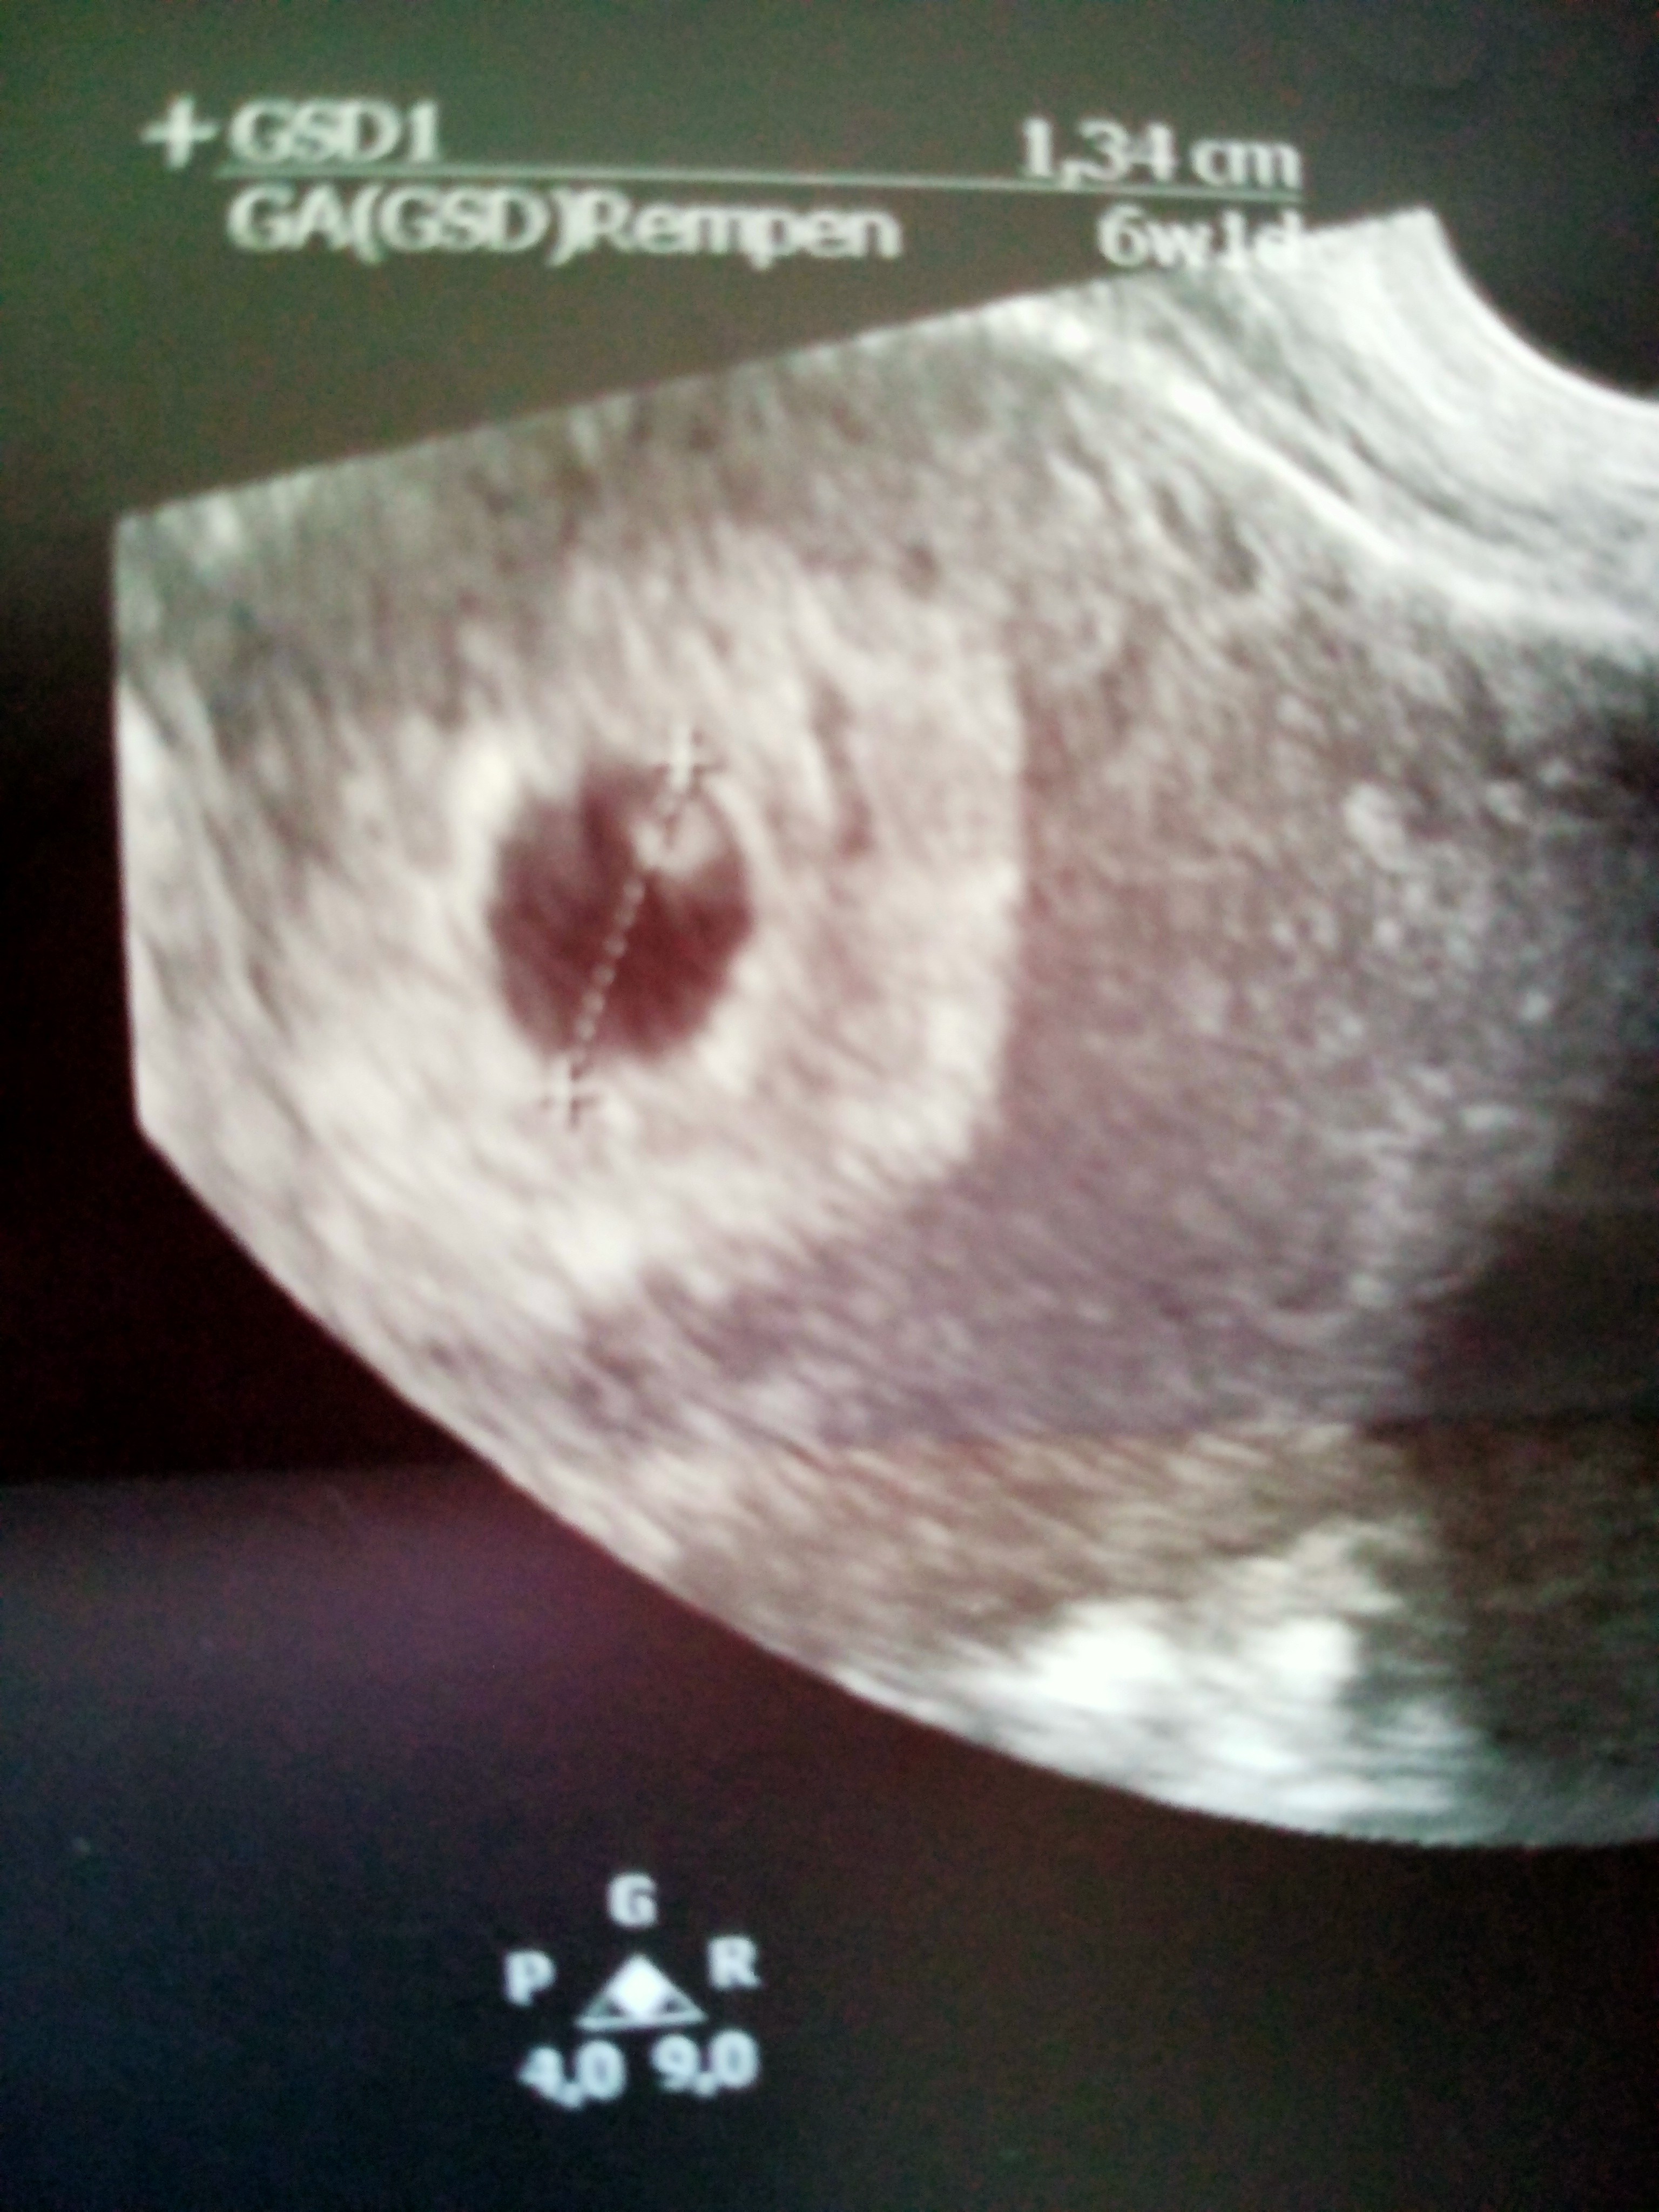

Hej mamusie. Powiedzcie mi czy tutaj jest jedenczy dwa pęcherzyki ? Z pierwszej wizyty w 5 tygodniu i drugie usgz 6 tygodnia. Ginekolog nic nie wspomniał żesą dwa za to przepisał duphaston i luteine. Czy tylko ja tam widzę dwa ?